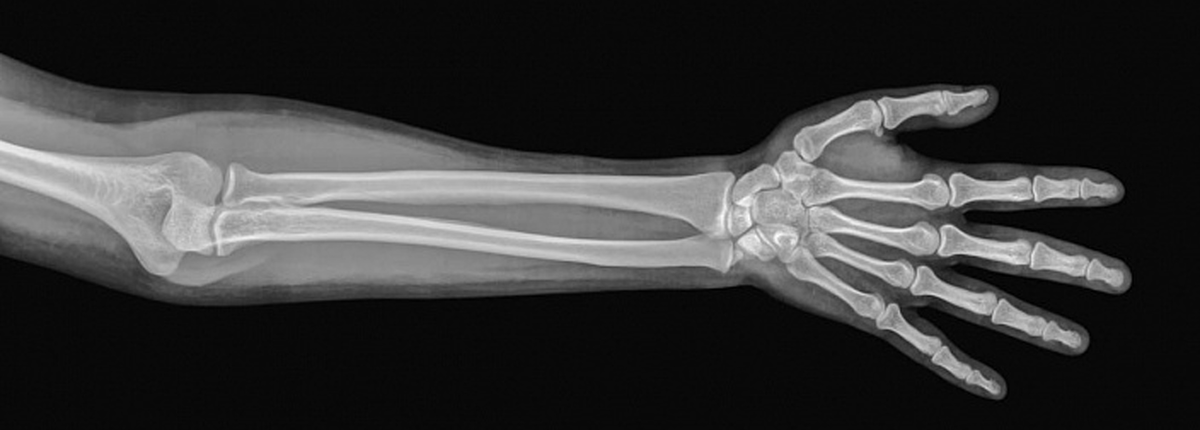

И наконец, самое пугающее: когда вы смотрите на рентгеновский снимок, вы видите себя... изнутри. Это напоминание, что, несмотря на кажущуюся крепость, наш скелет уязвим. Поэтому заботьтесь о своих костях: ешьте пищу, богатую кальцием, занимайтесь спортом и берегите свой остов, ведь он с вами на всю жизнь!